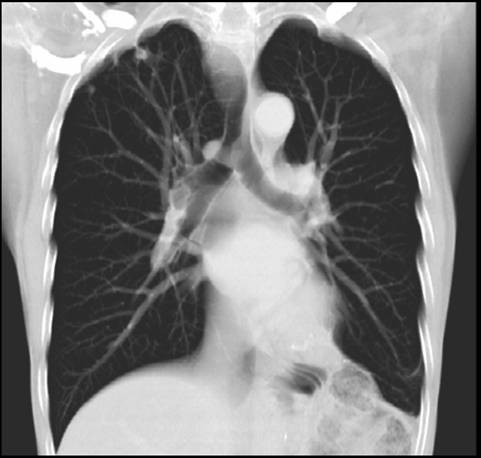

Radiology is a medical speciality that uses imaging modalities such as ultrasound, CT scanning and MRI scanning, to diagnose disease. There have been numerous high tech advances over the years and radiologists are specially trained doctors whose job it is to interprate the images and advise on which type of x-ray or scan is the best investigation in any given situation.

X-Rays were first discovered by Roentgen in 1895 and went into widespread use for medical purposes very soon afterwards. Recent years have seen an explosion of development in medical imaging with the availability of complex ultrasound, CT and MRI scanning. Even plain x-rays have evolved and instead of being printed on film are now more commonly viewed as digital images that can be manipulated on a computer workstation and sent around the hospital or around the world on computer networks such as PACS (picture archiving and communications systems).